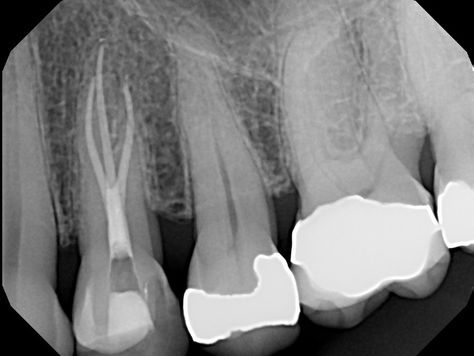

MB2 separate exit

Studies have found that over 90% of maxillary first molars have MB2 canals. Many of these canals join at the apex, but can you guess what...